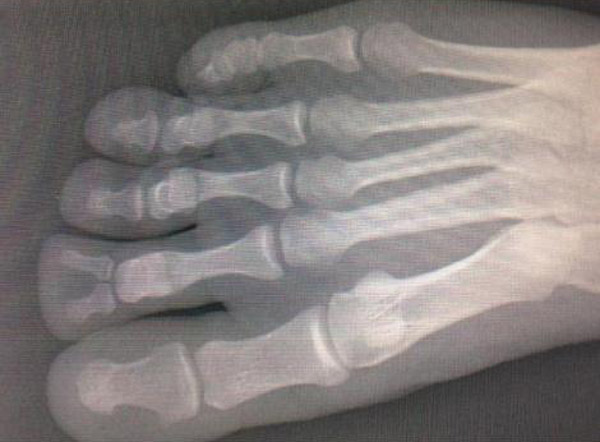

レントゲン写真「エイリアンの足」、この男の足は一体どうなっているのか(2枚)

gif_animation 「エイリアンの足」、とも呼ばれるレントゲン写真がある。一見普通の足のようにも見えるこの写真は、あるいは人類の進化の証か、それともただの奇形?[2]img